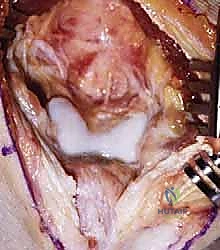

سُميت هذه العملية تيمناً بالجراحين اللذين قاما بتطويرها. تعتمد الفكرة الأساسية لهذه الجراحة العبقرية على مبدأ ميكانيكي بسيط ولكنه فعال للغاية. في الكوع المتيبس بسبب الخشونة، تتكون نتوءات عظمية في الجزء الأمامي (الناتئ الإكليلي والحفرة الإكليلية) والجزء الخلفي (الناتئ الزجي والحفرة الزجية).

بدلاً من إجراء شق جراحي أمامي وشق جراحي خلفي كبيرين للوصول إلى هذه النتوءات، يتم الوصول إلى المفصل من الخلف فقط. يقوم الدكتور هطيف بإزالة النتوءات العظمية الخلفية، ثم يقوم بـ إحداث ثقب (Fenestration) أو نافذة دقيقة في العظم الرقيق الفاصل بين الحفرة الزجية (الخلفية) والحفرة الإكليلية (الأمامية) لعظمة العضد.

هذا الثقب يحقق فوائد مذهلة:

1. يسمح للجراح بالرؤية والوصول إلى النتوءات العظمية الأمامية والأجسام الحرة وإزالتها من خلال هذا الثقب دون الحاجة لفتح الكوع من الأمام.

2. يخلق مساحة إضافية (فراغ) يسمح لطرف عظمة الزند بالدخول فيه أثناء فرد الكوع بالكامل، مما يزيل الاحتكاك ويزيد من نطاق الحركة فوراً.

3. يقلل الضغط داخل المفصل، مما يخفف الألم بشكل ملحوظ.